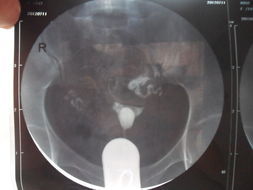

不同原因及不同程度的輸卵管病變治療方式是不一樣的,你的情況具體適應那一種方式需要看一下你的造影片子才能決定。你可以把造影片子上傳。